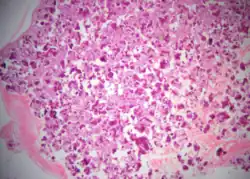

Cemento-ossifying fibroma is a well-demarcated lesion, often encapsulated by a thin fibrous capsule and sharply separated from adjacent normal bone. It shows significant internal variation, with differing amounts of fibrous and mineralized tissue—even within the same lesion. Mineralization is often more prominent centrally and typically includes osteoid, woven to lamellar bone, and dense basophilic cementum-like calcifications. Bony trabeculae may fuse into broad sheets or form thick, anastomosing strands. Osteoblastic rimming is commonly seen around bone trabeculae.[27]

The stroma is fibroblastic and may exhibit areas of hypercellularity and nuclear hyperchromasia; however, mitotic activity is rare and cellular atypia is minimal .[28] The mineralized component may include acellular or paucicellular cementum-like spheres along with bone structures .[28]

Well-defined fibrous connective tissue with calcified droplets and woven bone trabeculae, bordered by native lamellar bone.[3]

Ossifying Fibroma: Low-power photomicrograph shows a well-defined solid tumour mass composed of cellular fibrous connective tissue interspersed with cementum-like calcified droplets and trabeculae of bone.[3]